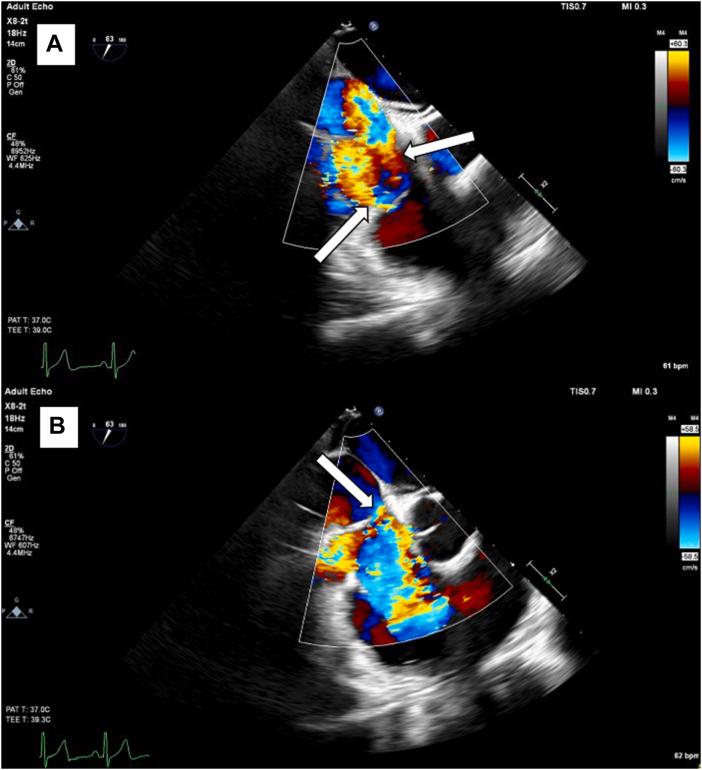

Cor Triatriatum Dexter Associated With a Dysplastic Tricuspid Valve.

• Cor triatriatum dexter results from persistence of the right valve of the sinus venosus. • A 3D evaluation can help differentiate CTD from other congenital abnormalities. • Treatment options for CTD include surgery, first line, or percutaneous resection.

• 右三房心由静脉窦右瓣持续存在引起。

• 三维评估有助于将右三房心与其他先天性异常区分开来。

• 右三房心的治疗选择包括手术(一线治疗)或经皮切除术。